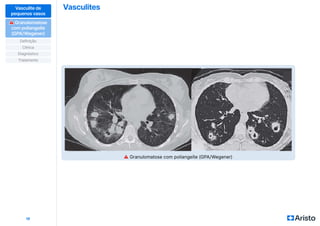

⚠ Granulomatose com poliangeíte (GPA/Wegener)

c-ANCA associada

Lesão de trato respiratório superior

Cavitação pulmonar, estenose

de traqueia, tosse e hemoptise

Hemorragia alveolar

Granulomas

Lesão de trato

respiratório inferior

Glomerulonefrite

pauci-imune

Acometimento de trato respiratório em 95% dos pacientes

Dor, drenagem piossanguinolenta,

queda da base nasal e úlceras